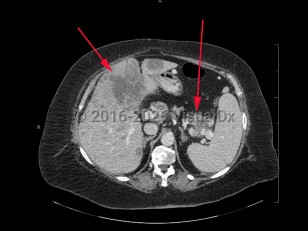

Metastatic pancreatic carcinomaMetastatic pancreatic carcinoma

Abdominal aortic aneurysmAbdominal aortic aneurysm

Aortic dissectionAortic dissection